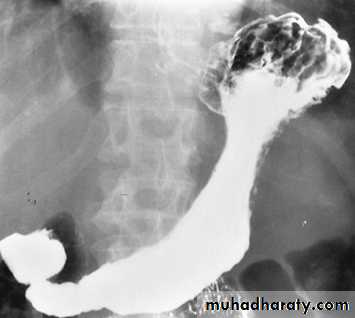

Achalasia

It is a neuromuscular abnormality result from failure of relaxation of the cardiac sphincter, which present at barium examination as a smooth , tapered narrowing always at the lower end of esophagus (bird beak or rat-tail appearance).There is associated dilatation of the esophagus, which often shows absent peristalsis. The dilated esophagus usually contains food residues and may be visible on CXR. The lungs may show consolidation and bronchiectasis from aspiration of the esophageal contents. The stomach gas bubble is usually absent.